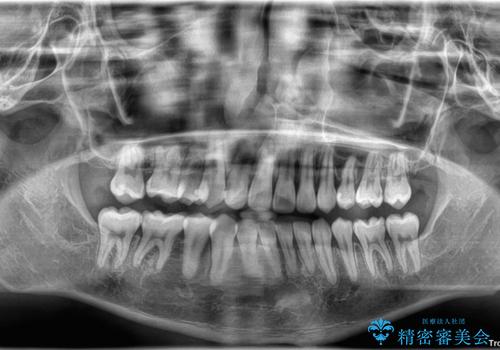

治療後には、デコボコと正中の位置が改善し、見た目だけでなく歯磨きがしやすい清潔なお口の環境を手に入れました。

上下左右の第一小臼歯を抜歯してスペースを確保する計画を立てました。

矯正装置には白いプラスチックブラケットと白いコーティングワイヤーを使用し、見た目にも配慮した治療を行いました。